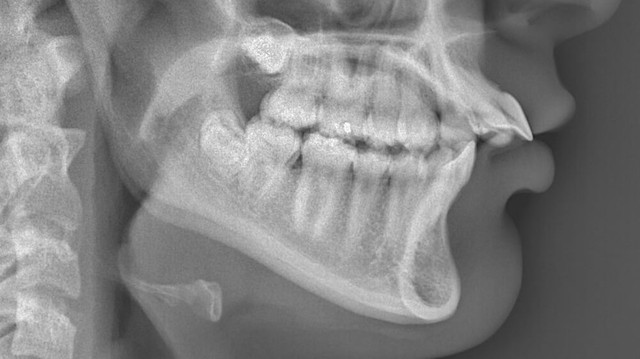

X-quang hàm chếch là một kỹ thuật hình ảnh y khoa quan trọng, giúp bác sĩ chẩn đoán và điều trị nhiều vấn đề liên quan đến vùng hàm mặt. Bài viết này sẽ giúp bạn hiểu rõ hơn về X-quang hàm chếch, từ quy trình thực hiện cho đến những lợi ích và hạn chế của nó.